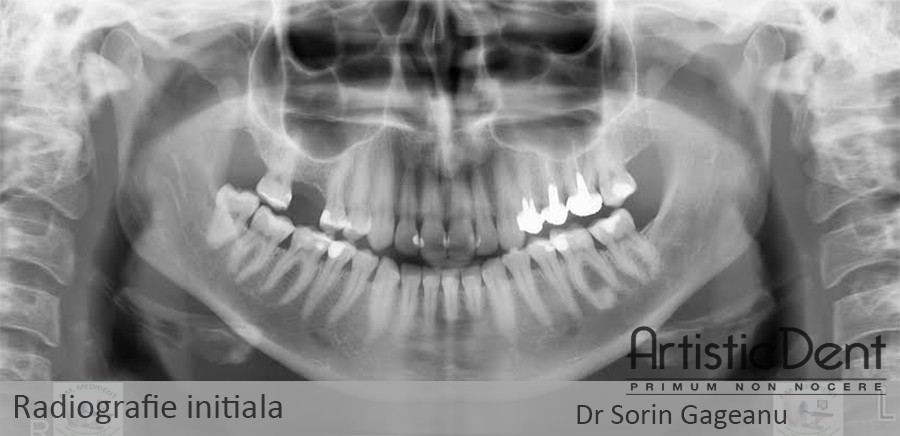

Va prezint un caz clinic tratat in clinica dentara Artistic Dent:

Pacienta prezinta lipsa osoasa verticala la nivelul molarului de 6 ani, avand o inaltime a crestei osoase de doar 4,5 mm. In tehnica clasica ar fi avut nevoie de o operatie de aditie osoasa tip “Sinus lift”. Cu ajutorul acestui implant dentar Straumann Roxolid rezistent de doar 4 mm lungime si 4,1 mm diametru, pacienta nu a mai avut nevoie de aditia osoasa tip Sinus lift.